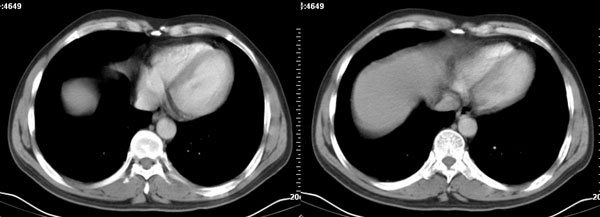

李**,男,46岁,便血1天入院,慢性贫血貌,腹平、软,剑突下压痛,肠鸣音稍活跃,hb大于1g/l,胃镜:慢性浅表性胃炎,b超:1肝内多发性占位 2腹腔内囊性肿块 ,肝内圆形影平扫ct值42.9,动脉期48.6,静脉期58.2,延迟期62.2

影像学表现:1 腹腔前中部、胰腺前方囊实性病灶(个人认为确定有否实性成分存在这是关键,涉及到鉴别诊断,如果是口服阳性造影剂则可明确左侧是不是小肠了),囊性部分囊壁不均,实性部分有强化,与小肠关系较密切,局部小肠受推移;与胰头、胃后壁均有脂肪间隙存在;2 胰腺无异常改变,胰周无渗出;3肝后段包膜下2个小圆形低密度灶,从图像和楼主提供的ct值来看有轻度强化,灶周无片状强化,不似单纯囊肿及肝癌、炎性病变表现;4 腹膜后及腹腔内无淋巴结肿大。

胰腺边界清晰,胰周筋膜不厚,胰周脂肪密度无明显增高;其前方囊实性病灶,边界清晰,增强后实性部分轻度强化;肝内多发边界清晰低密度影,增强后无明显强化(平扫ct值42.9,动脉期48.6,静脉期58.2,延迟期62.2)。

我们先确定病变来源于何处。从片上看,应该说是起源于肠道的囊实性的肿块。二、肝内低密度影,增强强化随时间强化,考虑小血管瘤。